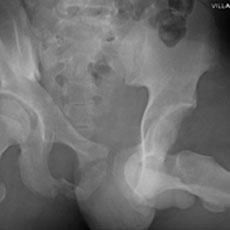

"Satisfaction of Search" Never Stop Looking -- Before and After Surgery

Current Concept Review

Daniel Y. Hong, Stephanie N. Moore-Lotridge, John J. Block, Hernan Correa, Jennifer L. Halpern, Ginger E. Holt, Christopher Stutz, Jeffrey E. Martus, Tim Schrader, Jonathan G. Schoenecker